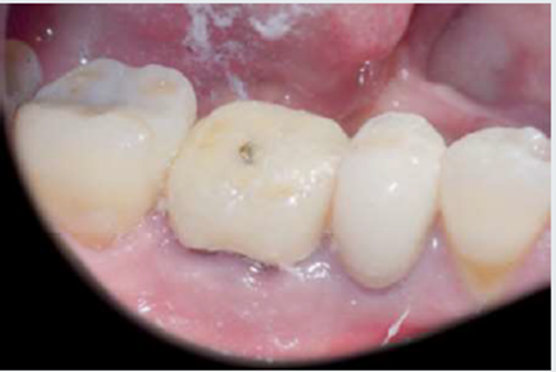

Um paciente do gênero masculino com 62 anos de idade, sem comorbidades, buscou tratamento odontológico relatando incômodo na região do dente 46, que possuía uma coroa provisória. Ao exame clínico, havia leve retração gengival ao redor do elemento dentário (Figura 1). Após os exames de TCFC e radiografia panorâmica, foram detectadas fratura radicular e lesão periapical correspondente (Figura 2).